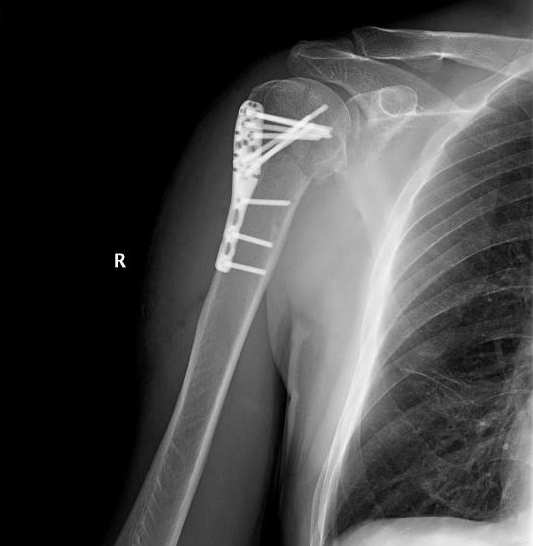

1. Открытый остеосинтез с использованием пластин:

• Установка металлической пластины и винтов для удержания костных фрагментов.

• Применяется при сложных переломах.